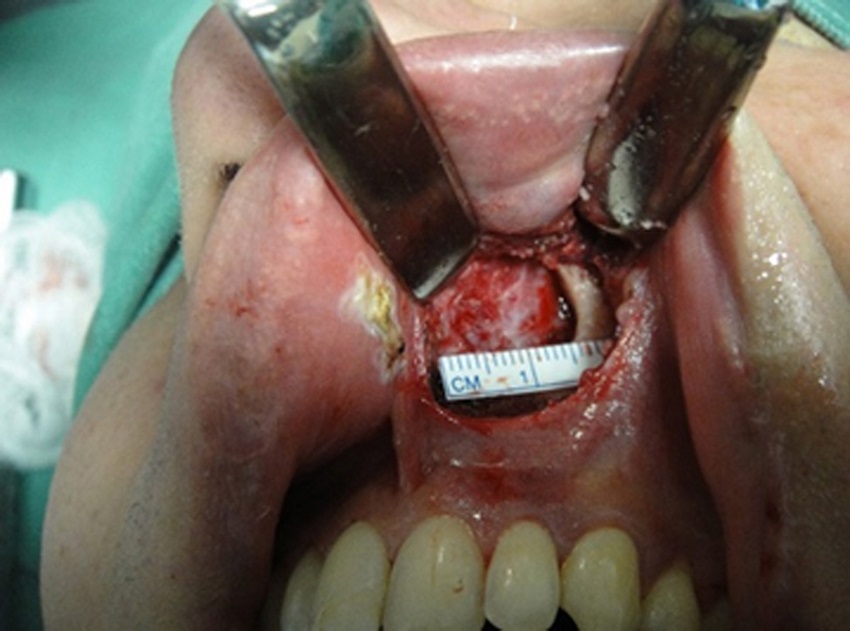

In a study that analyzed 88 noses of Korean individuals, mean values of 30.1 mm were found for men and 28 mm for women, transversally at the level of the pyriform aperture. The shape and size of the pyriform aperture exert a significant impact on the nasal breathing effectiveness. The size and shape of the nasal bones and the pyriform aperture can be used to clarify the anthropological characteristics of each race. The pyriform aperture of the Korean race is larger than that of the white race (Fig. 1).4

The treatment of nasal obstruction attributed to nasal valve dysfunction is typically aimed at interventions addressed to the internal or external nasal valve component. A 2015 study indicates that these patients can attain respiratory function improvement through surgical correction at the level of the pyriform aperture. Of twenty-six patients undergoing pyriform plasty surgery, 23 (88%) reported a significant improvement in their nasal obstruction bilaterally. The other 3 (11.5%) had a less significant improvement. The result of this study was obtained subjectively through a self-administered questionnaire. In this study, measurements using CT scan showed values of 23.6-25.32 mm in men and 22.6-23.7 mm in women.5

Surgical technique

Three months after being submitted to surgery, the patients returned and answered the NOSE questionnaire, to the same examiner, and were submitted to postoperative rhinomanometry with the same equipment, with and without vasoconstrictor agent.